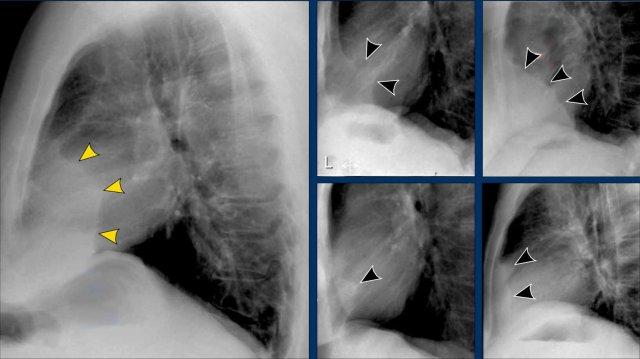

- Trên tư thế PA, có thể nhận thấy rốn phổi to, nhưng khó phân biệt giữa giãn mạch máu và hạch to.

- Trên tư thế nghiêng, sự hiện diện của các đám mờ tròn ở những vùng mà mạch máu phổi bình thường không có mặt gợi ý mạnh mẽ đến hạch bạch huyết to.

Trong trường hợp này, bệnh nhân được chẩn đoán sarcoidosis.

Ngoài ra, lưu ý dải cạnh khí quản dày, một dấu hiệu khác của hạch to trung thất.

To rốn phổi – ca 1

Trong trường hợp này, bóng rốn phổi to ra ở cả hai bên. Nguyên nhân có thể do mạch máu giãn to hoặc hạch bạch huyết to. Một dấu hiệu rất có giá trị trong trường hợp này là khối nằm bên phải khí quản.

Đây được gọi là dấu hiệu 1-2-3 trong bệnh sarcoidosis, tức là to rốn phổi trái, rốn phổi phải và hạch cạnh khí quản.

Dưới đây là thêm một số ví dụ về bệnh sarcoidosis.

Nhấp vào hình để phóng to.

- Hạch bạch huyết to và hình ảnh kính mờ (ground-glass) ở phổi

- Hạch bạch huyết to, dấu hiệu 1-2-3

- Hạch bạch huyết to khối lớn

- Dấu hiệu 1-2-3

- Hình ảnh nốt ở phổi, không có hạch bạch huyết to

- Hạch bạch huyết rốn phổi và cạnh khí quản to